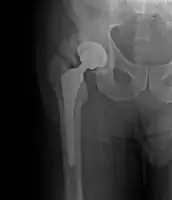

- Locations

- Hip most common - typically after ORIF (52% any grade, 19% Grade III-IV) or THA (43% any grade, 9% Grade III-IV)

- Randomized. 161 patients. Preop RT 7/1 (<4 hours) vs. Postop RT 17.5/5 (<=96 hours). Portals periacetabular and intertrochanteric soft tissues

- Randomized. 249 patients, high risk. Post-op RT 10/5 vs. 17.5/5. Portals periacetabular and intertrochanteric soft tissues

- Randomized, multi-institutional. 98/122 patients with risk factors, following elective hip replacement. Treated with pre-op RT 7-8/1 <4 hours vs. post-op RT 7-8/1 <48 hours. Fields to soft tissues between periacetabular region of pelvis and intertrochanteric portion of femur. Median F/U 9.5 months

- Randomized. 62 hips in 55 patients at high risk. Treated with postop RT 8/1 vs. 10/5 limited field (includes lateral aspect of greater trochanter). Minimum F/U 6 months